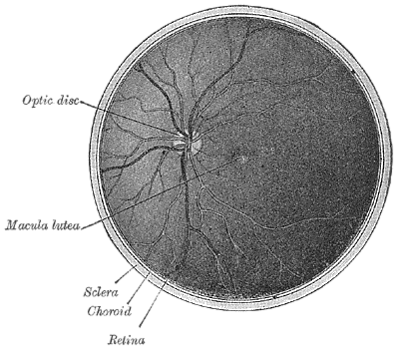

Диск зрительного нерва или головка зрительного нерва является зоной выхода для аксонов ганглиозных клеток сетчатки. Поскольку в этой зоне не могут располагаться фоторецепторы, то в этом месте имеется «зона нечувствительности», называемая слепое пятно. Его диаметр — примерно 5,5 угловых градусов, расстояние от «центральной ямки» (зоны наиболее плотного расположения колбочек в центре сетчатки) примерно 16 угловых градусов.

Аксоны ганглиозных клеток сетчатки образуют в месте выхода из глаза зрительный нерв, по которому сигналы от сетчатки передаются на следующие уровни обработки в зрительной системе. Обычно зрительный нерв состоит из 1-1,2 млн аксонов. Диск зрительного нерва является также точкой входа для крупных кровеносных сосудов, питающих сетчатку.[1]

Диск зрительного нерва размещён в 3 × 4 мм от носовой части ямки. Это вертикальная, овальная, со средними размерами 1.76 мм по горизонтали и 1.92 мм по вертикали.[2] Существует центральный депрессия, переменного размера, называется глазная чаша.